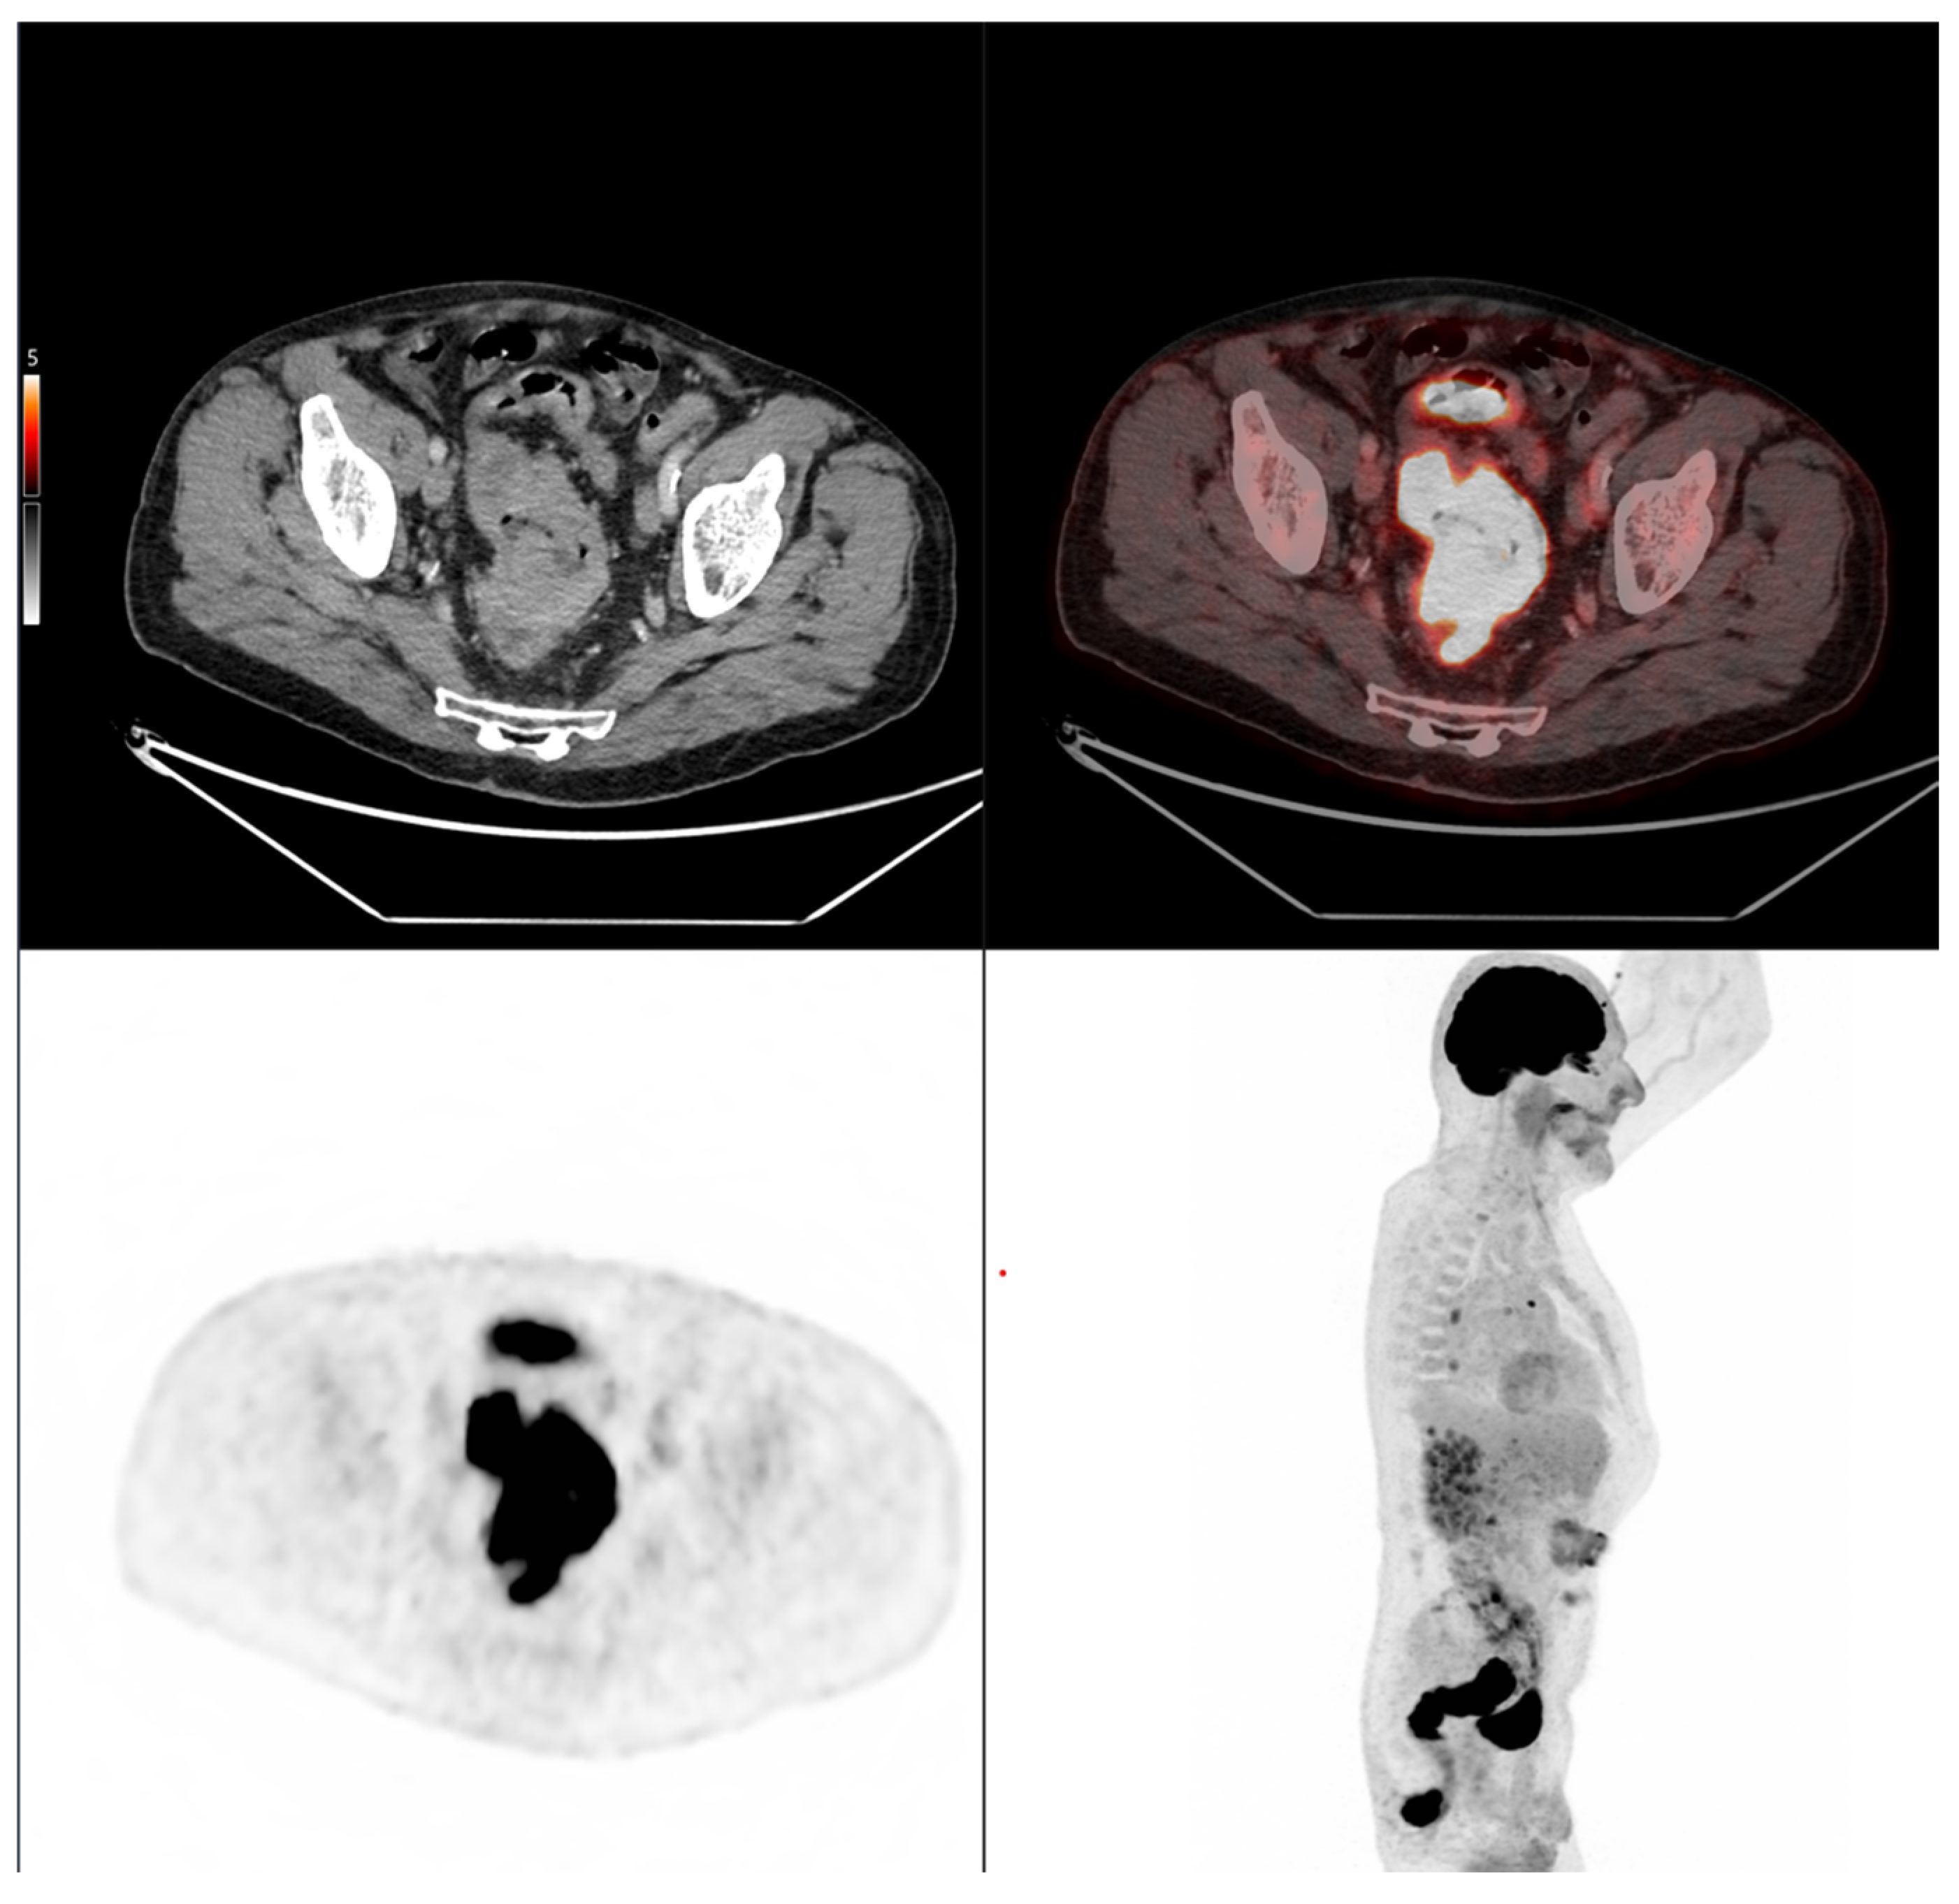

Case 2: A 69-year-old patient with stage IIA rectal cancer, presenting with a semi-circumferential primary tumor with craniocaudal extension and MTV both below the predictive cut-offs (5.1 cm vs. 6.2 cm; MTV 10.1 vs. 35.49 for OS and 32.08 for PFS). Baseline FDG PET/CT (top row) revealed intense hypermetabolism (SUVmax 38.8). Interim FDG PET/CT (bottom row) showed a good partial metabolic response, and the patient experienced sustained clinical benefit with no progression in the long term (OS = PFS = 29 months).

Figure 7. Representative example of manual delineation of a primary rectal tumor on baseline FDG PET/CT showing manual delineation of the metabolically active tumor volume (first row) on the PET image with corresponding fused PET/CT image and CT image with iodinated contrast medium (second row). Morphological features, including tumor shape (circular or semi-circular), cranio-caudal extension (in cm), and overall tumor volume (in cm3), were assessed on the CT image (often with contrast medium) coregistered with the PET images. Tumor shape was determined on the axial plane, cranio-caudal extension on the sagittal plane, and tumor volume after careful delineation on all planes. Iodinated contrast medium was administrated in 70% of cases after exclusion of contraindications. Metabolic parameters, including SUVmax, SUVmean, MTV and TLG, were systematically extracted from the segmented tumor (yellow in this figure). SUVmax (M in this figure) and TLG were automatically displayed. SUVmean could be obtained by simply replacing SUVmax with SUVmean in the parameter selection. MTV was automatically calculated from TLG and SUVmean values displayed on the workstation. The highlighted region in yellow represents the 3D contour of the primary tumor, excluding physiological uptake and non-tumor regions.